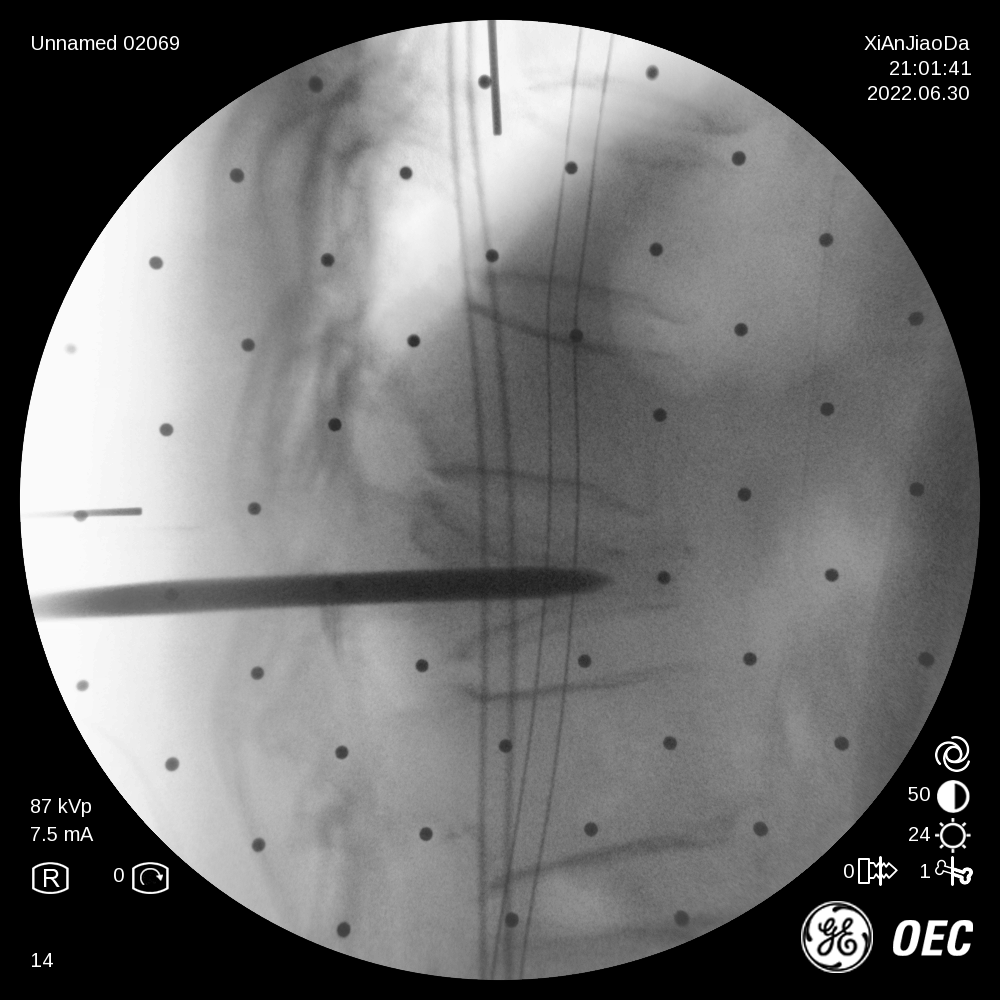

在该机器人辅助手术过程中,仅需通过正侧位进行伤椎识别,通过软件将正侧位透视图与术前规划数据的结合,即可得到病人伤椎的姿态以及实际的穿刺角度,之后机械臂根据软件参数进行精准定位,手术医生在机械臂引导下一次性进针成功,并对进针位置角度表示满意,整个过程少于20分钟,实现了手术的更精准化、高效化。相较于传统定位流程,术前规划只能保存在医生脑海中,术前与术中流程无法很好的衔接,术中穿刺依赖医生丰富的经验,对于情况复杂的病人,术中需要反复试验,导致手术时间延长、患者受辐射量增加。后续放置球囊、注入骨水泥等操作则同传统手工操作。